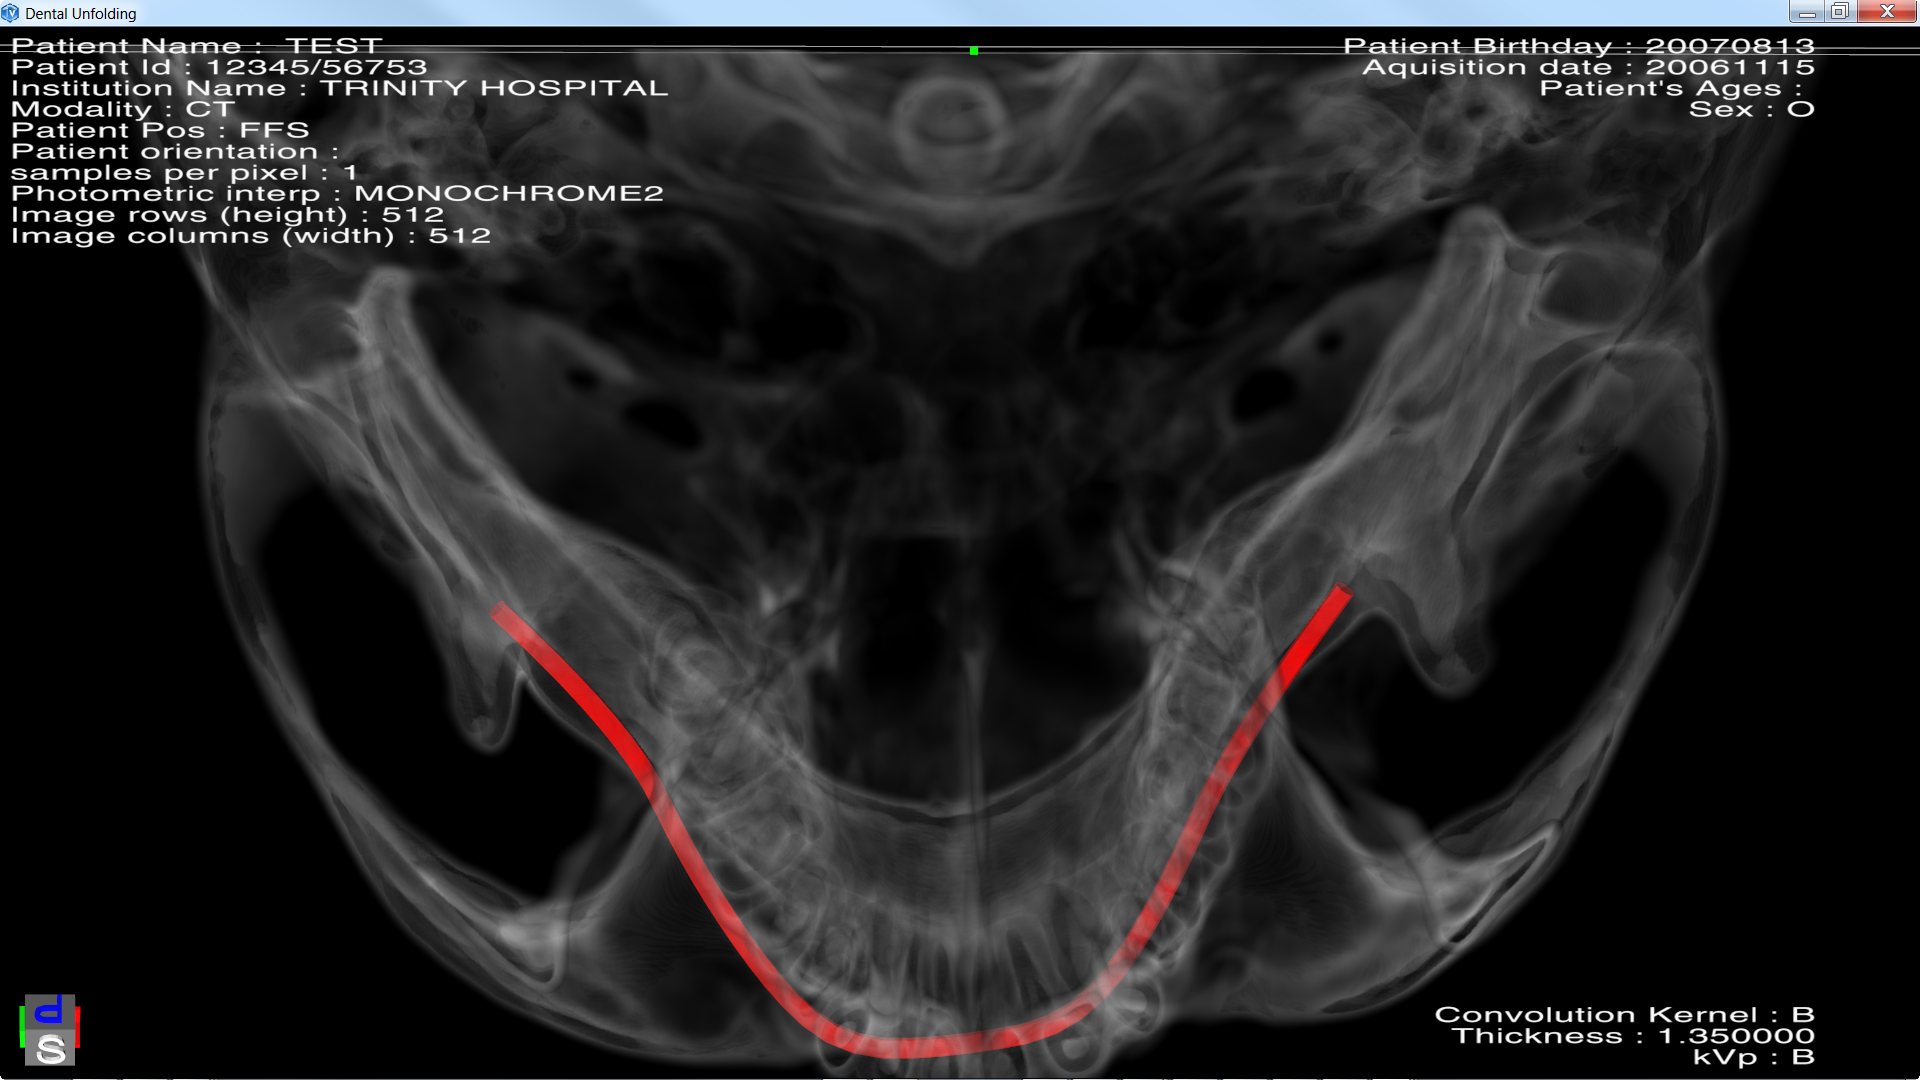

Here we use this solution to unfold a jaw along with a predefined spline. Then after we get a rendering like a Dental Panoramic X-Ray. By using the SoROIManip we can change the slab thickness and its position.

Pressing 'U' activates unfolding animation and pressing 'S' stops it. We also used the Average Intensity Projection along the slab. You can change this render mode by changing the renderMode field of SoVolumeRender.

After unfolding. We get the resulting Slab. This Slab can be modify by using the ROI manipulator.